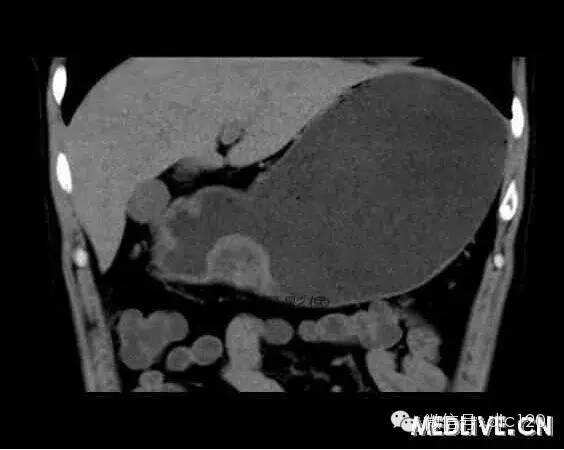

男,36歲,間斷性返酸噯氣3年,3個(gè)月前出現(xiàn)上腹疼痛,饑餓時(shí)加重。圖1-3為CT平掃,圖4-6分別為CT增強(qiáng)掃描的動(dòng)脈期、門脈期和延遲期。影像表現(xiàn) CT檢查可見(jiàn)胃幽門前區(qū)胃小彎側(cè)胃壁局限性增厚、隆起或伴凸向胃腔內(nèi)的小結(jié)節(jié)灶,寬基地,境界光整,注射對(duì)比劑,增強(qiáng)掃描后,CT值可達(dá)50HU以上,與正常胰腺?gòu)?qiáng)化相仿。 確診依據(jù) 手術(shù):異位于胃的胰腺 鑒別診斷 1、